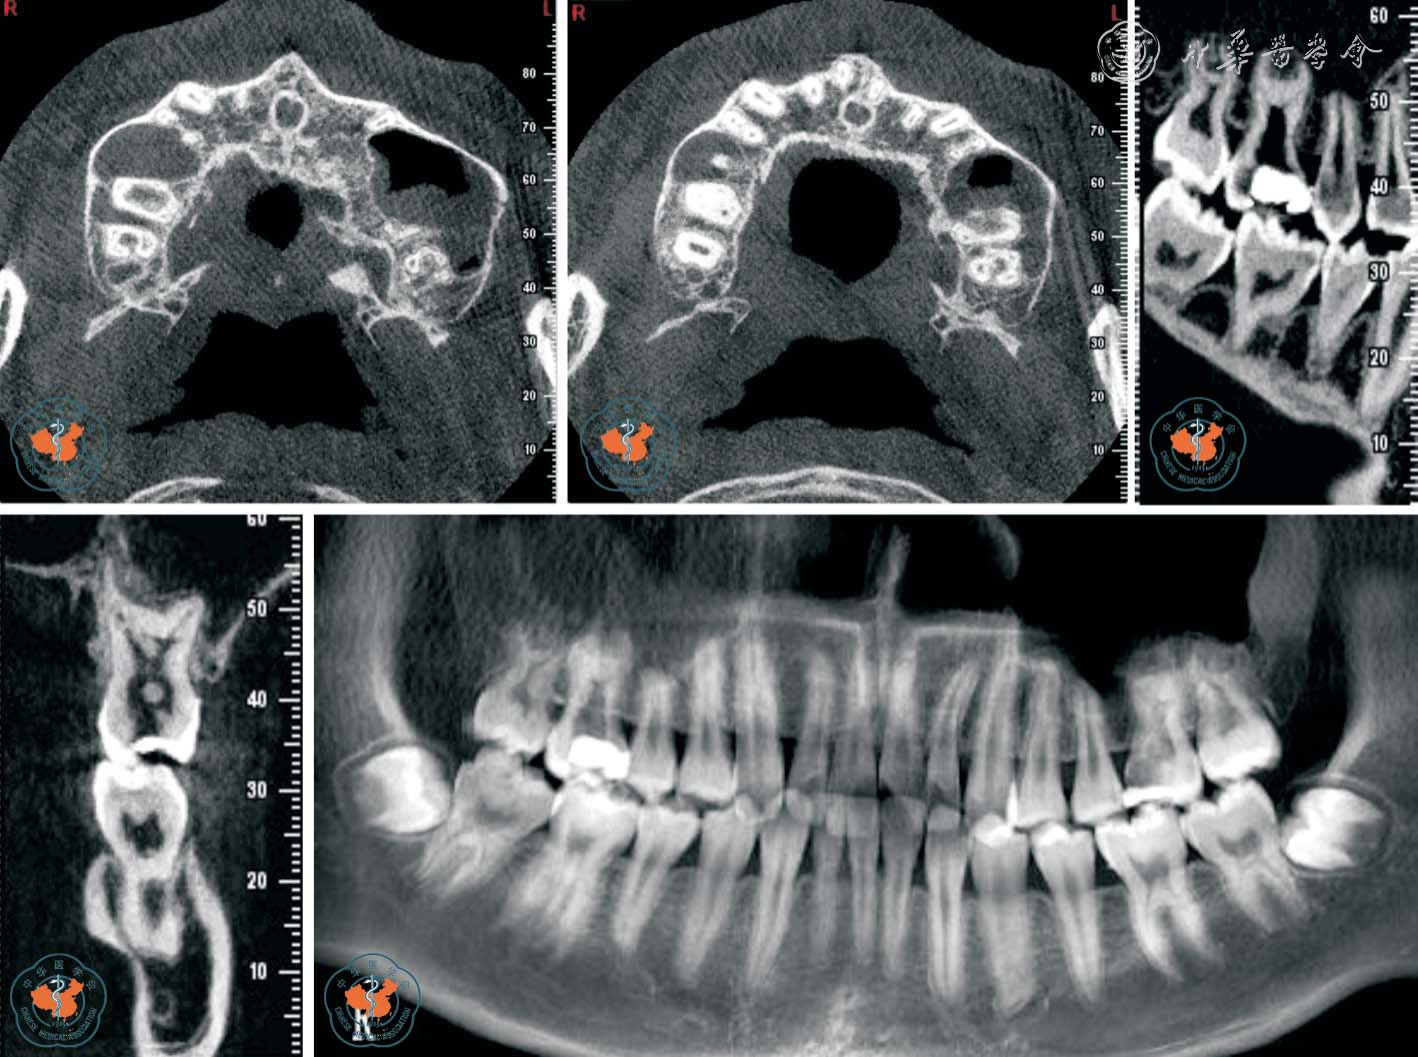

1. 正确判断根管数目: 根管数目的正确判断是根管治疗成功的主要因素之一。 Baratto Filho 等11采用体外研究、临床研究和CBCT 三种方法分析了上颌第一磨牙的根管解剖。 体外研究表明,140 颗离体牙中67.12%存在第四根管,其中1 例有7 个根管,存在第四根管的磨牙中92.58%第四根管位于近中颊根。 临床研究表明,53.26%及0.35%的磨牙分别存在4、5、6 个根管, 并且95.63%发生于近中颊根。 CBCT 研究表明,1.85%、37.05%、1.85%的磨牙分别存在2、4、5 个根管。 同时CBCT 对变异根管的发现和定位具有重要意义。 临床医师在根管治疗术前及术中可随时调用和调整CBCT 局部三维重建图像,从不同角度及层面观察根管的融合和分支情况,了解根管的形态、数目、走向、根尖处根管的位置是否融合等,是指导复杂根管系统牙齿治疗时的重要影像手段(图1 ~2)。

图1 CBCT 轴位显示左上颌第一磨牙5 个根管,其中侧支根管未根冲

图2 CBCT 轴位、VR 及MPR 重建冠、矢状位图像显示上颌中切牙变异根管